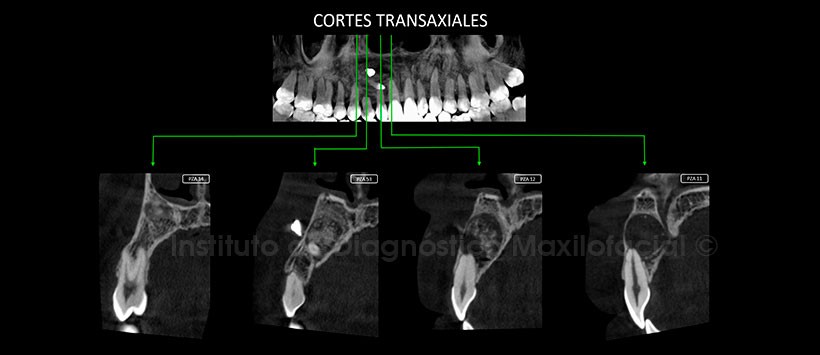

En los cortes transaxiales y tangenciales (Figura 3 y Figura 4), observamos que esta lesión es de límites definidos, bordes corticalizados y cuenta con calcificaciones internas. Condicionando en las estructuras adyacentes, un aparente adelgazamiento del conducto nasopalatino y reabsorción radicular externa leve de la pieza 12.